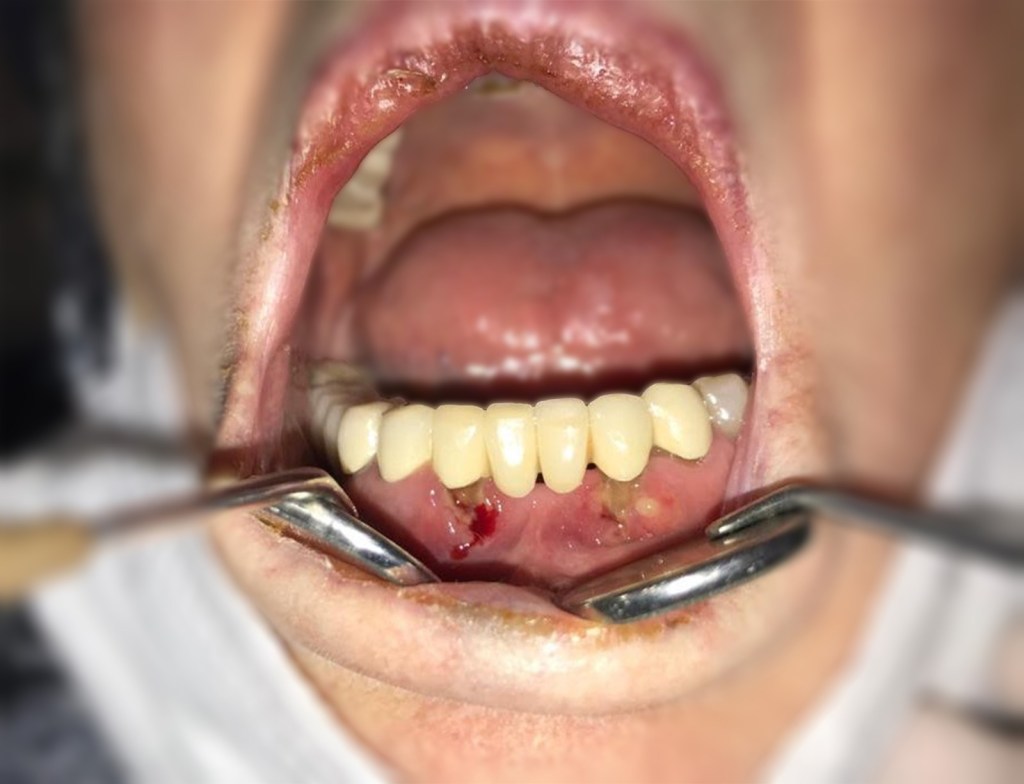

5- İlerlemiş periodontal hastalık ve nekrotize ülseratif periodonal hastalık: COVID-19’un sistemik bulguları ortaya çıktıktan sonra veya önce gelişebilen ve enfeksiyon sonrasında da devam edebilen agresif periodontal hastalık rapor edilmekte ve rutin dental klinik işleyişinde sıklıkla göze çarpmaktadır. COVID-19 ile beraber periodontal hastalık hızlanmakta ve kemik destrüksiyonu artmış bir şekilde karşımıza çıkmaktadır (Şekil 1). Ayrıca periodontal hastalığın bir çeşidi olan dental papil nekrozunun ve ağrının görüldüğü nekrotize ülseratif form da rapor edilmiştir.”